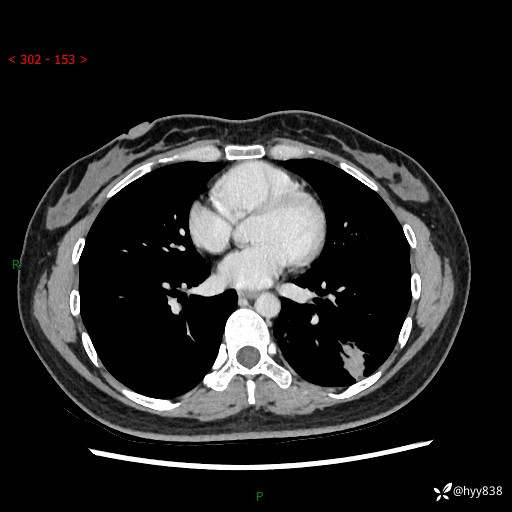

【患者信息】:36岁/女

【主诉】:左侧下胸部阵发性疼痛2周,乏力1周

【现病史及既往史】:患者自诉2周前饮酒后出现左侧下胸部阵发性疼痛,不随呼吸改变,无咳嗽咳痰、头晕头痛、咳血、呼吸困难等不适,于当地第一人民医院查胸部CT提示肺部感染,随后前往我院门诊给予抗感染(左氧氟沙星)治疗1周,自诉胸痛较前好转,感乏力、头晕,偶尔干咳,无咳痰,无发热、畏寒、胸闷、咯血、四肢酸痛、腹泻、腹痛等不适,门诊复查胸部CT提示:左肺下叶感染,病灶较前增加增大,遂以“肺部感染”收入我科。 起病以来,患者精神、饮食、睡眠可,大小便正常,体力体重无明显变化。

【检查】:胸部CT增强(外院平扫)